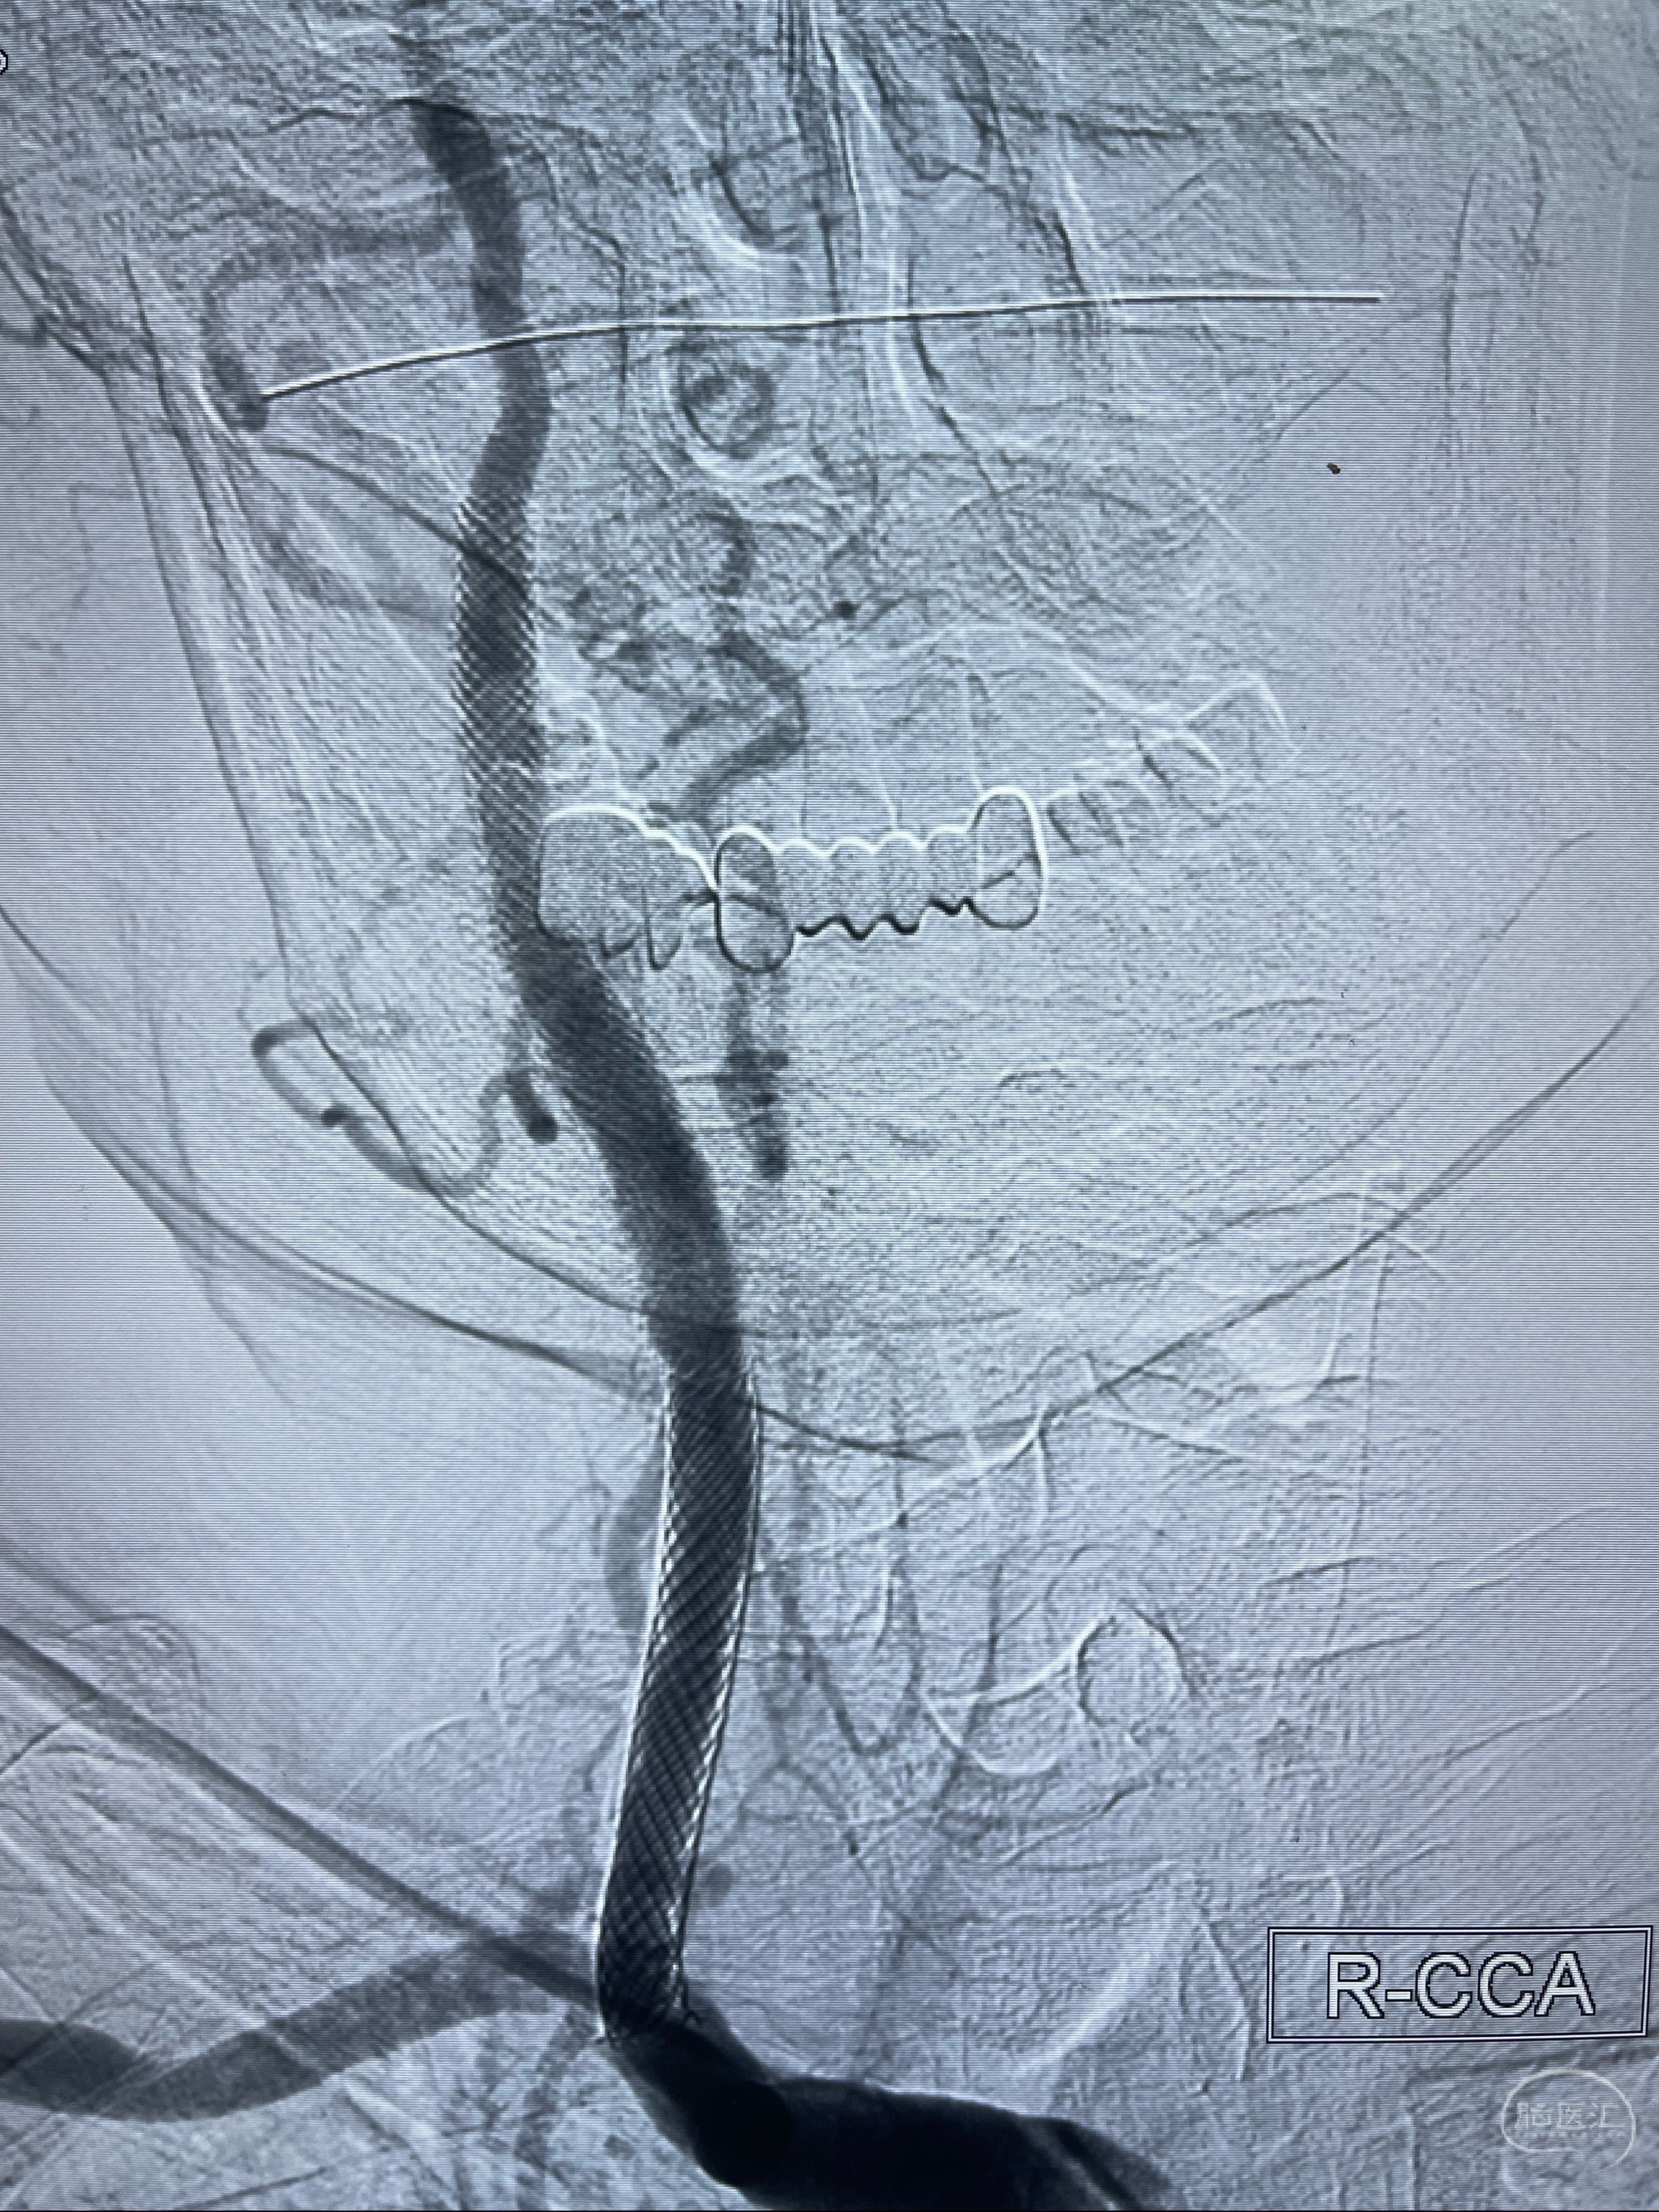

088NeuroMAX100cm长鞘在125cmMPA及黑泥鳅导丝引导下超选择性插入右侧颈内动脉支架内

经导引导管造影显示支架远端颈内动脉不规则狭窄伴局部充盈缺损,同时行全身肝素化5ml

泄除球囊造影显示局部管腔扩张佳

后移球囊至颈段狭窄段,以8-12个大气压扩张,持续30s后泄除球囊

即刻造影显示狭窄扩张佳

重新行“路径图”,支架导管在微导丝引导下超选择性插入至右侧颈内动脉眼段,4.5-50mmLeo支架释放,远心端位于海绵窦段,近心端位于岩骨段狭窄段以近

即刻造影显示支架贴壁佳

路径图下,5.5-50mmLeo支架导管在微导丝引导下超选择性插入远段Leo支架内

两枚支架部分重叠

多次确认支架位置及打开贴壁情况

支架完全打开,近心端位于原颈动脉支架远心端内